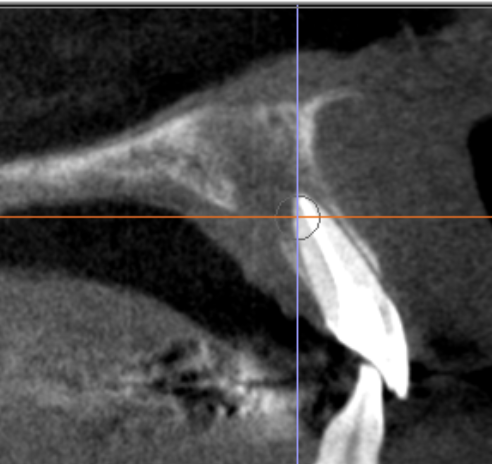

診断の鍵はCT(CBCT)|「2つの病変」を見極めて治療戦略を分ける

前歯部の病変は平面レントゲンだけでは重なりが生じやすく、

「根尖性病変なのか」「嚢胞が主体なのか」「併発なのか」が分かりにくいことがあります。

当院ではCT(CBCT)を用い、

- 根尖部の感染(根尖性歯周炎)

- 切歯管周囲の嚢胞性病変(切歯管嚢胞)の関係を立体的に評価し、原因に合わせて治療を組み立てます。

術後経過|3ヶ月で骨ができてきている所見を確認

術後3ヶ月の時点で、画像上、骨形成(骨ができてきている)ことを確認しています。

骨の治癒・成熟は数ヶ月〜年単位で進むため、今後も定期的に経過を追いながら